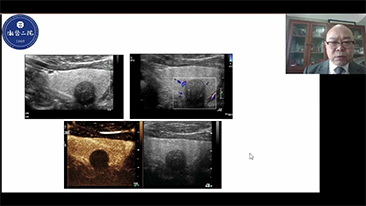

General Imaging

Mindray Resona General Imaging solutions help clinicians realize more accurate and efficient diagnosis and treatment results through comprehensive subdivision application probes and efficient clinical application tools.

General Imaging Products